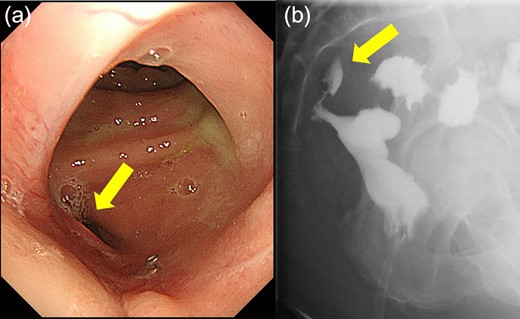

Case 1 was a 71-year-old man with a BMI of 29.7 kg/m2. Laparoscopic low anterior resection (LAR) and ileostomy was performed for rectal cancer in 2017 years. Postoperative fever and lower abdominal pain were noted, and colonoscopy was performed, and anastomotic leakage was noted with a correction of about 1/2 around the 6 o’clock direction of the anastomotic region, and fistula and formation of a large abscess cavity. After identification (Fig. 1), a tube was inserted for drainage and conservative treatment was performed. The patient was discharged on POD 46. Four months after the operation, marked improvement in the abscess cavity was noted but still remained (Fig. 2a and b). Anastomotic leakage was almost improved by colonoscopy at 17 months after surgery, but at the preference of the patient we performed colostomy 22 months after surgery (Fig. 3). It took a long time to improve intestinal movement of the colon because the large intestinal tract had not been used for a long time, and conservative treatment was performed using a nasogastric tube for paralytic ileus. Diet was initiated 7 days after surgery, and the patient was discharged from the hospital 14 days after surgery. The Wexner score [2] was 19 points one month after closure, 17 points 3 months after the operation and 16 points after 6 months after the operation, and severe anal dysfunction was observed, but gradually improved.

(a) Colonoscopy shows a fistula (arrow). (b) Enema examination shows a cavity (arrow) leading from the fistula.